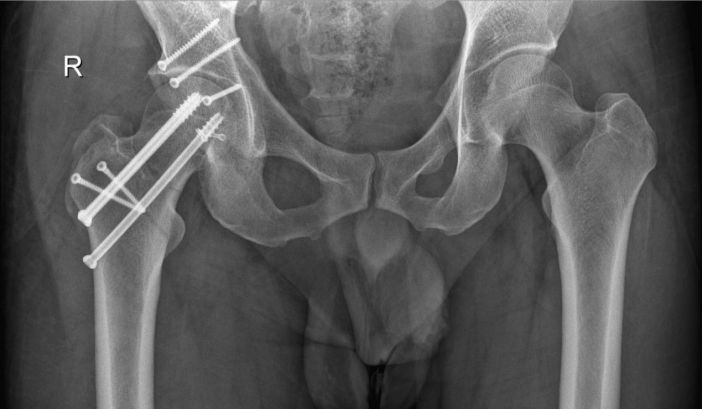

△術後

4月24日,吳主任帶領團隊按術前設計的方案,采用大轉子截骨入路,按部就班地進行手術操作。在西門子三維術中CT引導下,手術每個步驟都力求完美,對骨折部位進行精準複位。整個手術奮戰了5個小時。術後複查,骨折複位均達到解剖要求。術前患者家屬還向醫護人員送了紅包,醫護人員給予退還,患者家屬深表感謝。